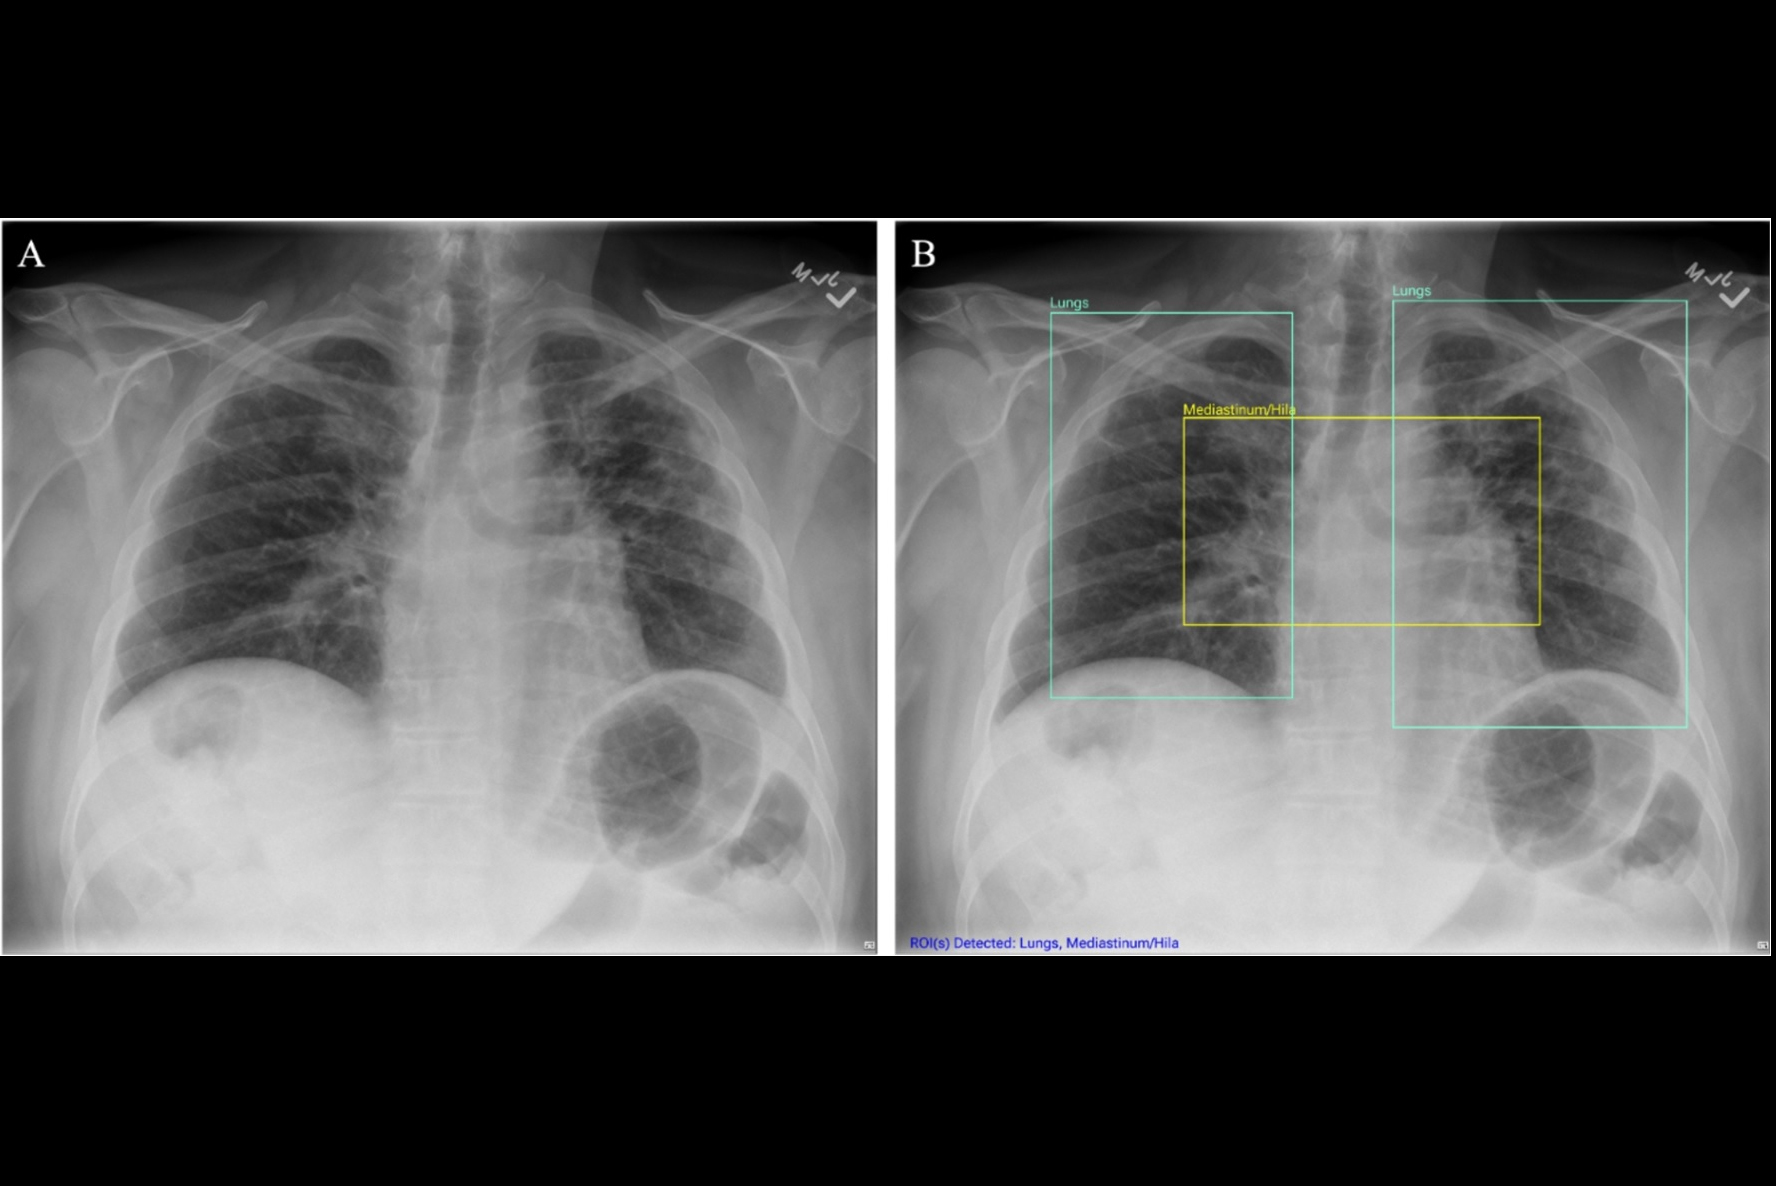

“These local explanations directly guide the physician to the area of concern in real-time. In our study, the AI literally put a box around areas of pneumonia or other abnormalities," Ye said.

Chest x-ray examples of (A, C) local (feature-based) AI explanations and (B, D) global (prototype-based) AI explanations from a simulated AI tool, ChestAId, presented to physicians in the study. In all examples, the correct diagnostic impression for the radiograph case in question is “right upper lobe pneumonia,” and the corresponding AI advice is correct. The patient clinical information associated with this chest radiograph was “a 63-year-old male presenting to the emergency department with cough.” To better simulate a realistic AI system, explanation specificity was changed according to high (i.e., 80%−94%) or low (i.e., 65%–79%) AI confidence level: bounding boxes in high-confidence local AI explanations (example in A) were more precise than those in low-confidence ones (example in C); high-confidence global AI explanations (example in B) had more classic exemplar images than low-confidence ones (example in D), for which the exemplar images were more subtle.